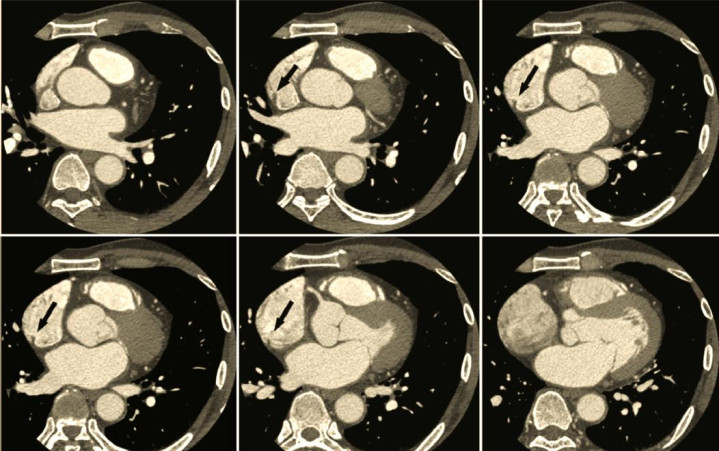

3. 亮血与黑血工夫:让结构更分明

通过不同的脉冲序列设想,不错赢得不同对比度的图像。亮血工夫(如稳态解放进动序列)使快速流动的血液呈现亮白色,而相对静止的心肌则呈现暗灰色,从而能明晰地描写出心腔的概括,用于评估腹黑的削弱功能和室壁畅通。黑血工夫(如快速自旋回波序列)则未必相背,它使血流信号隐藏呈玄色,从而能更明晰地披露心肌、血管壁和瓣膜等结构,用于不雅察心肌水肿、脂肪浸润或心包增厚等轻细病变。